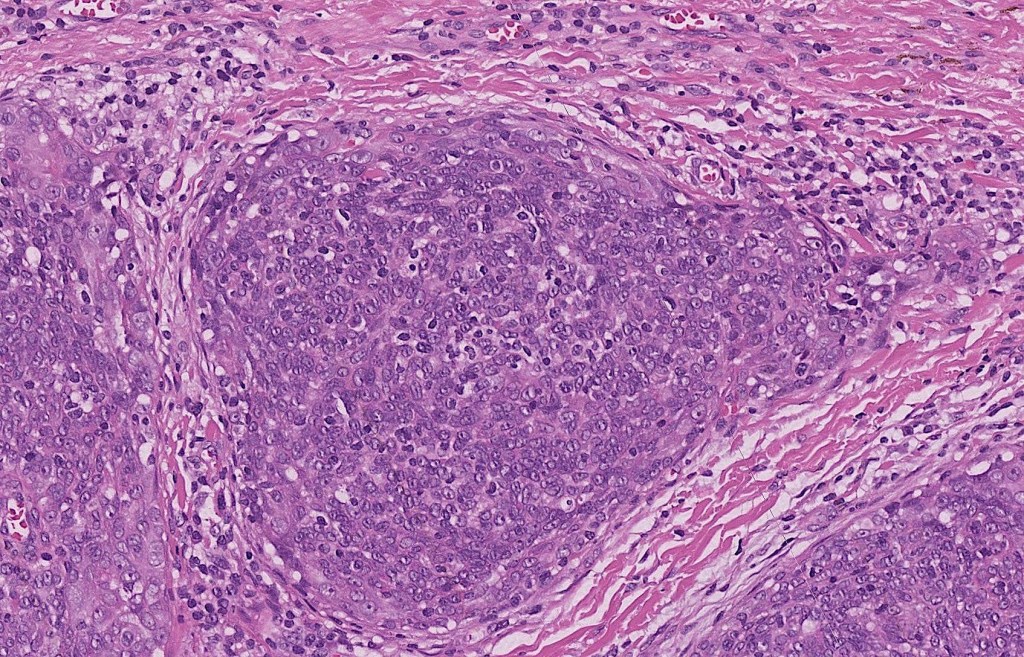

•Dermal generally circumscribed tumor nodule (less often it may show an infiltrative border)

•Syncytial epithelial component in nests, cords or sheets surrounded by an intense lymphoplasmacytic infiltrate

•Epithelial cells are large with abundant cytoplasm and vesicular nuclei with conspicuous nucleoli